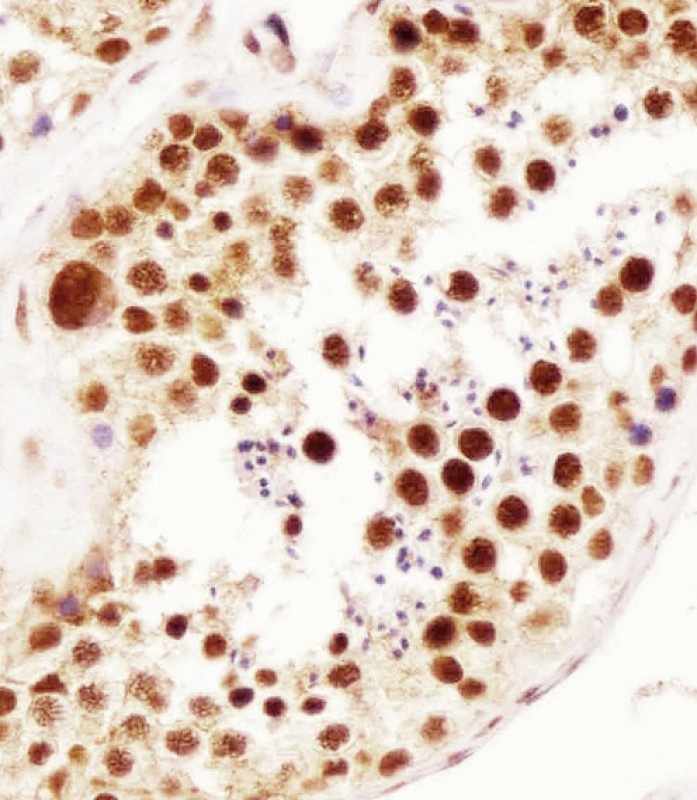

Immunohistochemistry of paraffin-embedded human ovary tumor slide using orb395161 (HuR Antibody) at dilution of 1:50.